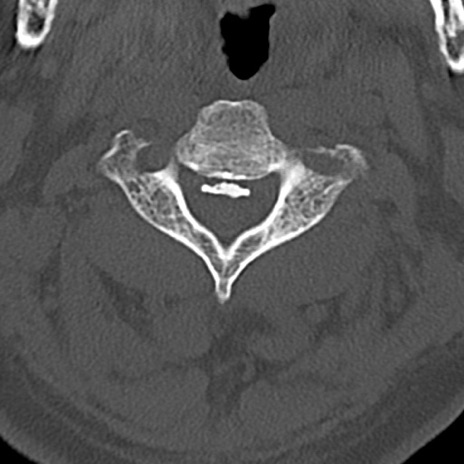

頚椎CT

横断像